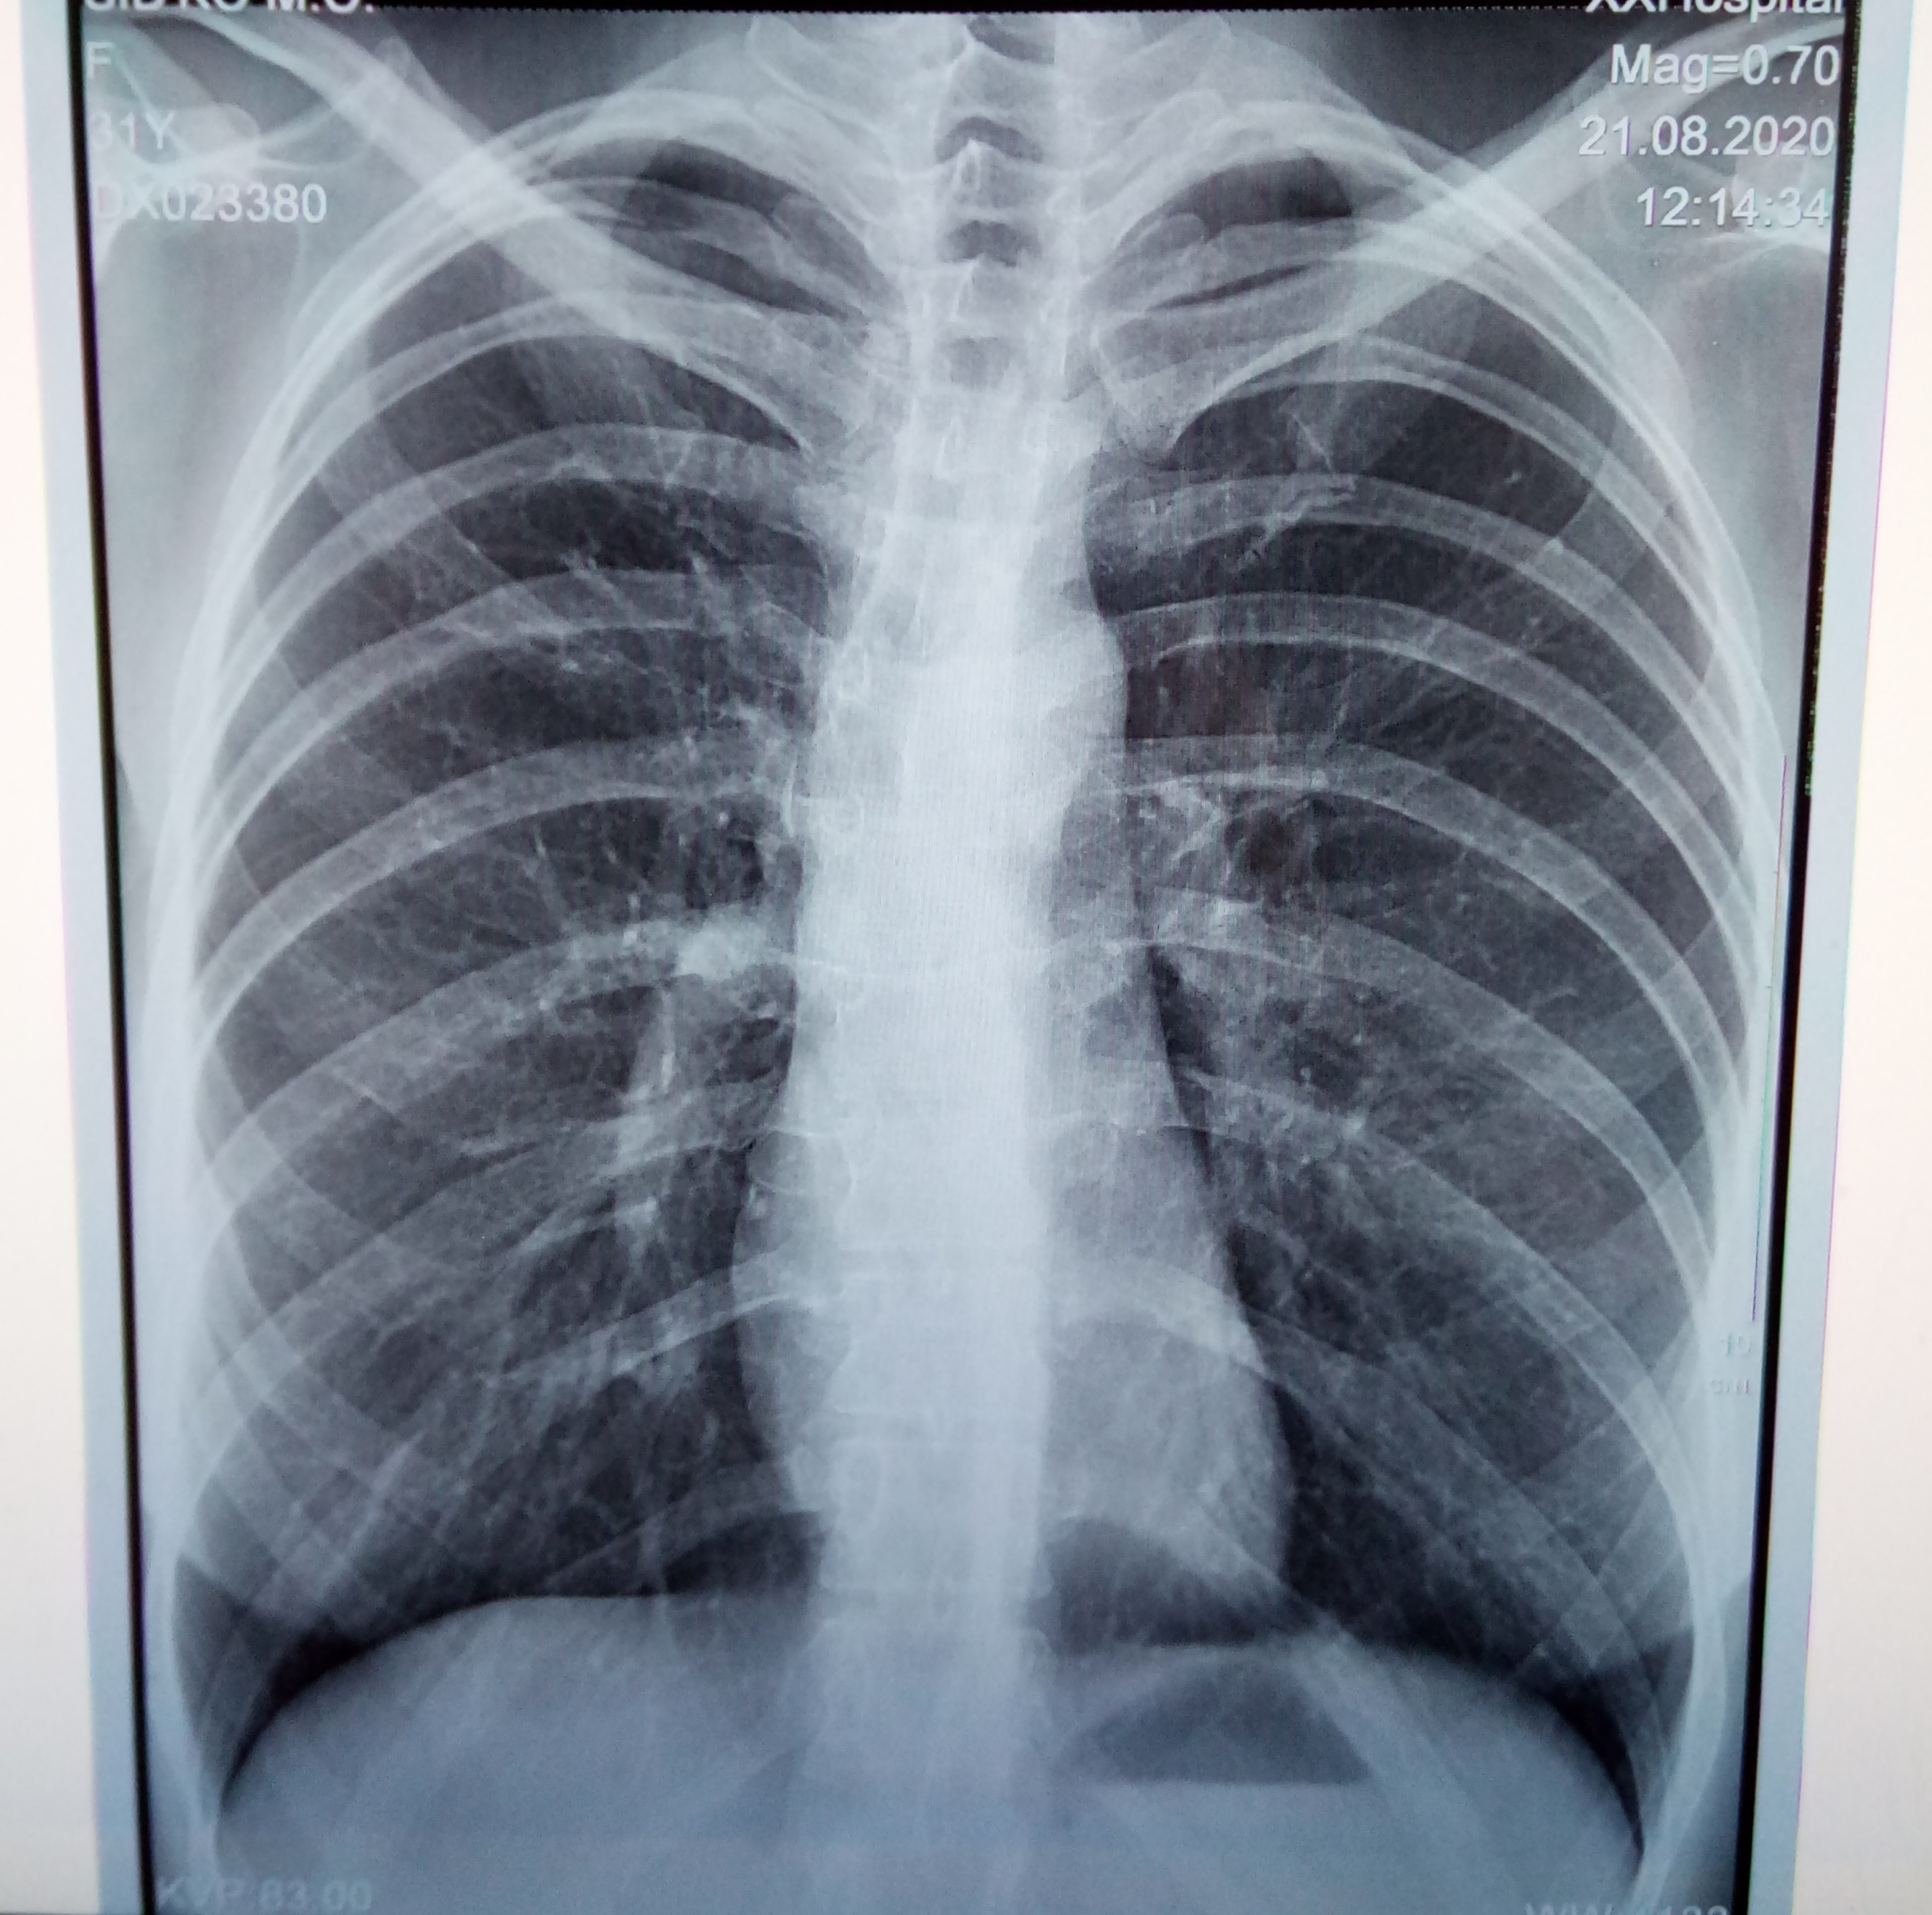

Нормальная рентгенограмма легких: что нужно знать

Раздел: Мудрость в объективе